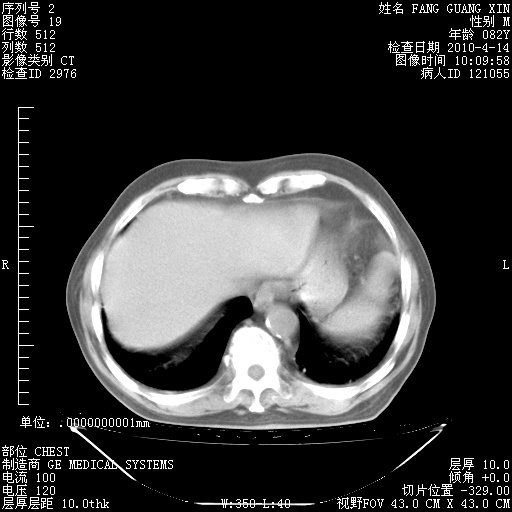

4月14日肺部CT